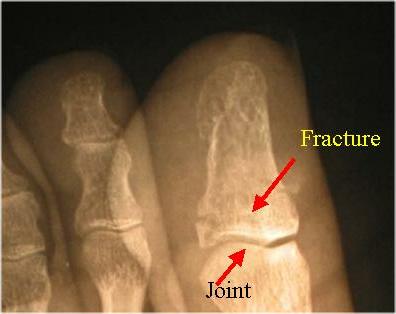

Examination by emergency medical people at a local hospital revealed the diver has a broken toe (comminuted fracture of the left first digital phalange). Basically, the toe was crushed into multiple fragments. Fortunately, this transverse fracture required no pinning or surgery. This type of fracture tends to heal rather well, but this diver missed diving for eight weeks while his body repaired the damage.

The X-rays below of the injury to the diver's left foot show multiple breaks (fine lines) at the in the first bone  (upper right of oblique view) of the big toe

X-Rays of Comminuted Fracture Caused By A Falling Scuba Cylinder

Oblique View

Enlarged Oblique View